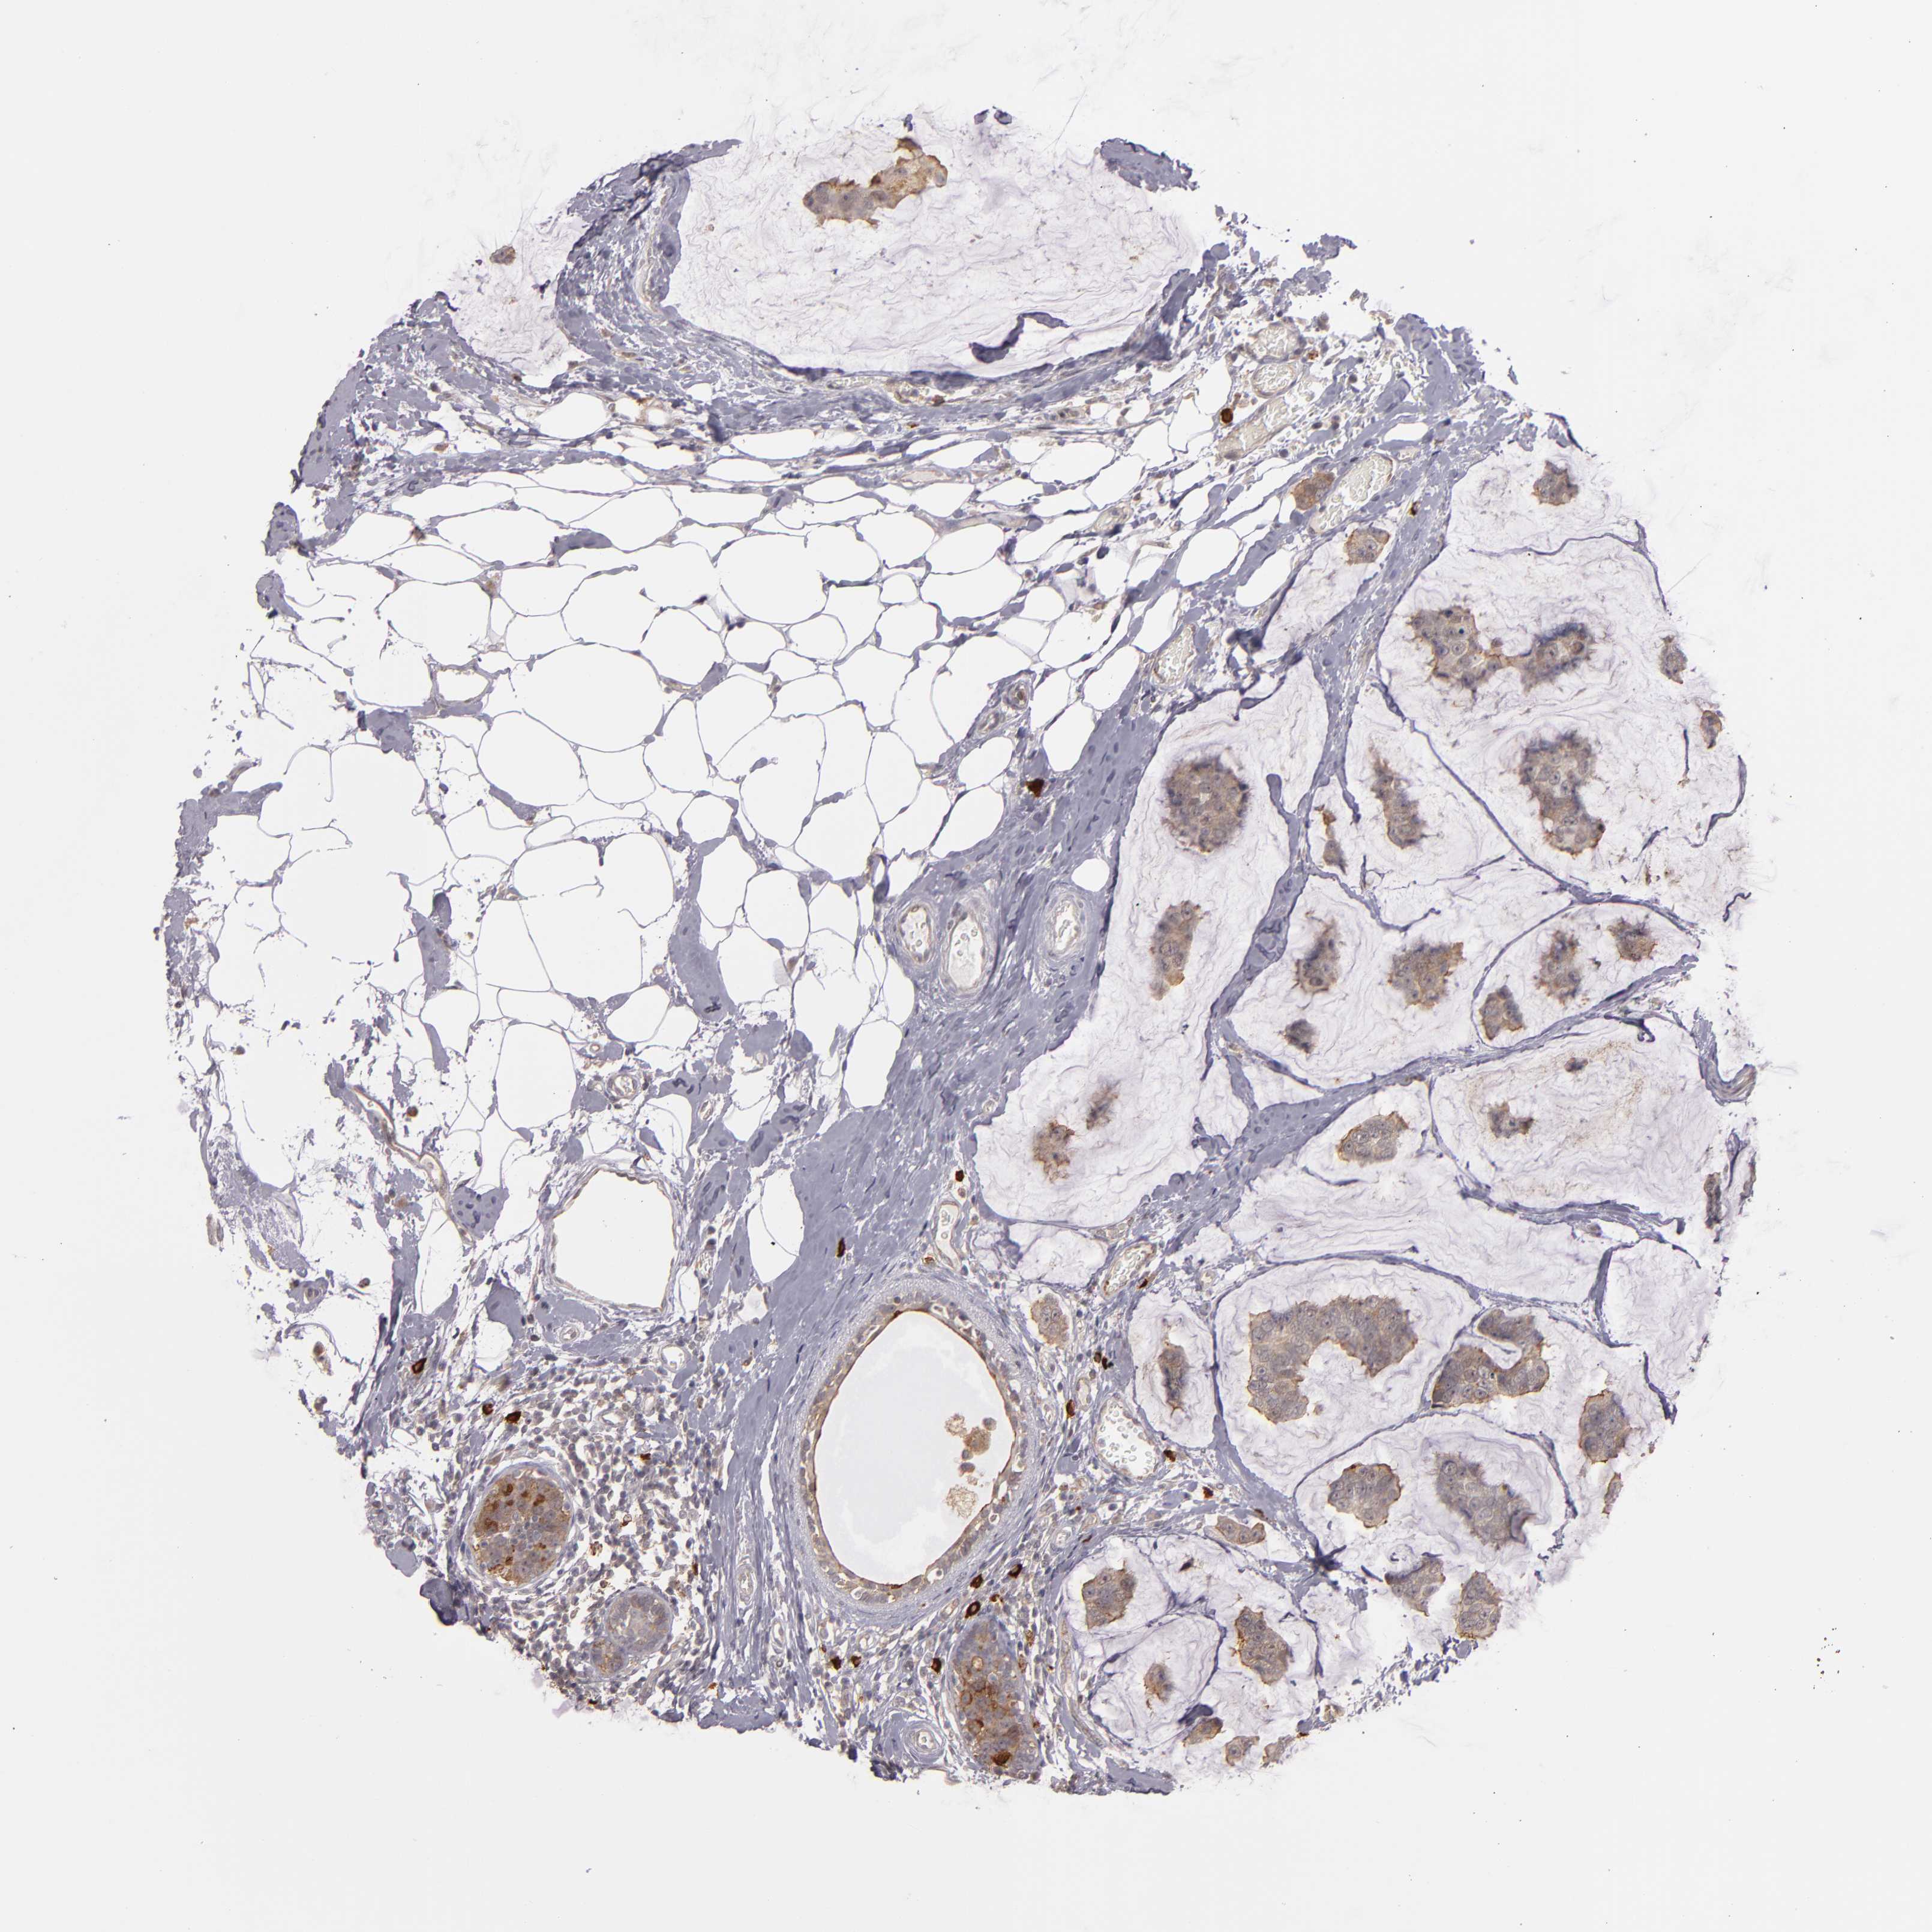

CANCER BREAST CANCER Show tissue menu

BRCA TCGA BRCA VALIDATION PROTEIN EXPRESSION